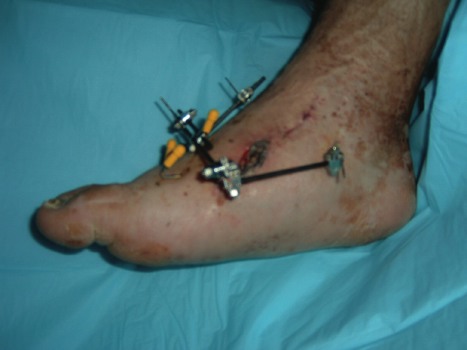

A 58-year-old patient with longstanding diabetes and a previous history of ulceration and neuropathy presented to the outpatient clinic with complaints of increasing redness and swelling to his right foot. He related that his primary care physician had seen him due to concern for a foot infection. However, the physician ordered X-rays and subsequently told the patient he had a fracture. The physician placed him on oral antibiotic therapy and sent him to the podiatry clinic for further workup. The patient denied any direct trauma to the foot or excessive changes in activity level. He complained of mild pain and admitted to fluctuating blood glucose levels. His past medical history was significant for diabetes, neuropathy and hypertension and no tobacco history. Physical examination revealed an obese male with palpable pedal pulses to the left foot and non-palpable dorsalis pedis on the right foot with a bounding posterior tibial pulse. He had absent protective and vibratory sensation bilaterally with increased skin temperatures to the right foot. The right foot was erythematous dorsal to the second through fifth metatarsals and edematous. We noted no ulcerations, macerations or fissures. Radiographs revealed dorsal dislocation at the tarsometatarsal joint, resulting in a divergence of the joint complex. We proceeded to emphasize cast immobilization until we achieved a reduction of edema and an equilibrium with the skin temperatures of the lower extremities. We continued the oral antibiotic therapy with Keflex in order to prevent infection due to deep bleeding from the fracturing or skin irritation from the edema. However, the tarsometatarsal was freely mobile and remained unstable during the four-week immobilization period. Due to the instability, we discussed surgical arthrodesis. We pursued this by using percutaneous Steinman pinning and a Synthes mini external fixator to add a structural framework around the fusion site. We added bone morphogenic protein at the arthrodesis sites to promote fusion. We subsequently emphasized non-weightbearing in a posterior splint and weekly clinic visits for pin care until the patient achieved radiographic union. At that time, we removed the fixation and initiated progressive weightbearing in a removable cast boot (i.e. CAM walker) for three to four weeks. We repeated radiographs and once we determined that the patient had maintained osseous integrity, we placed the patient in extra-depth shoes with custom-molded insoles for long-term maintenance. Dr. Hadi is an Associate with the Department of Podiatry of the MedClinic Medical Group in Sacramento, Calif. Dr. Steinberg (pictured) is an Assistant Professor in the Department of Surgery at the Georgetown University School of Medicine in Washington, D.C.